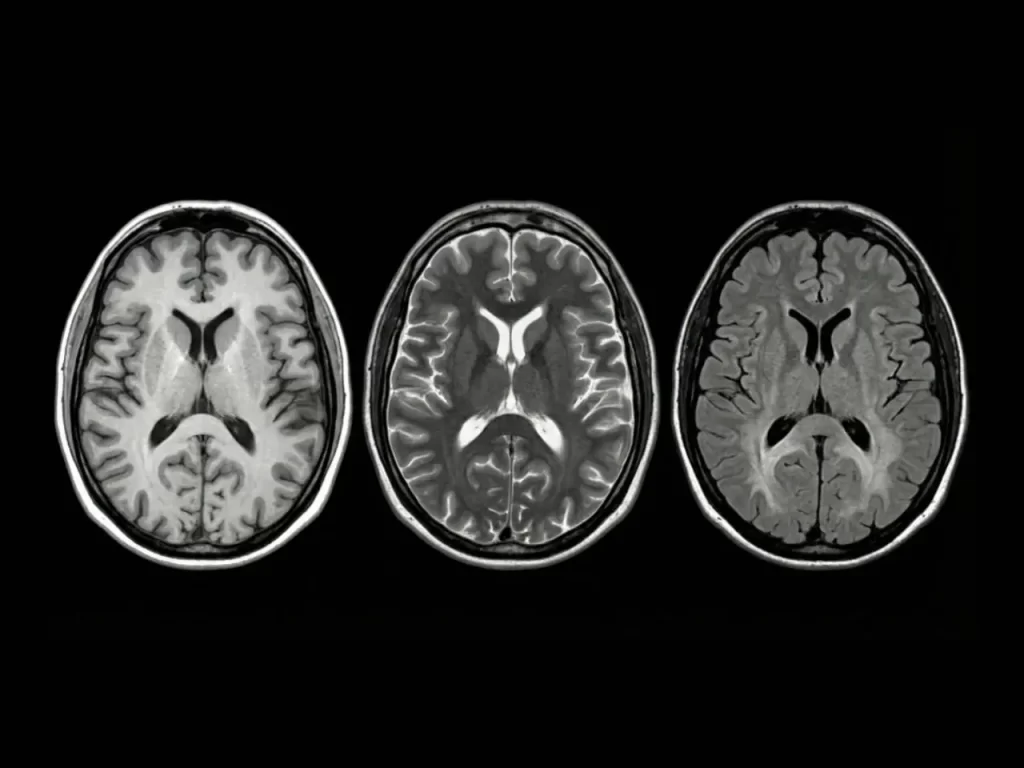

El impacto del ultrasonido focalizado en el cerebro

Originalmente, la técnica de FUS se investigaba para tratar la depresión grave y la anorexia nerviosa. Sin embargo, su aplicación en el Alzheimer sugiere que las ondas magnéticas podrían estar reactivando circuitos neuronales o facilitando la eliminación de placas proteicas asociadas con la demencia.